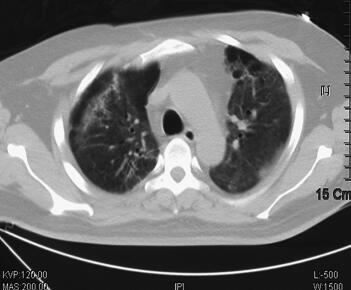

辅助检查:2011年4月5日胸部CT示双肺感染(图1)。血气分析:pH 7.40,PCO2 38.2mmHg,PO2 35.6mmHg,22.9mmol/L,BE −0.7mmol/L,SBE −1.0mmol/L,SaO2 65.0%,提示低氧血症;血常规:WBC 16.8×109/L,Hb 172g/L,PLT 56×109/L,N 0.917;急诊生化:ALT 89IU/L,TBTL 49.0μmol/L,Glu 7.64mmol/L,UREA 14.30mmol/L,CREA 132μmol/L,cTnI 0.04ng/ml。

图1 2011年4月5日胸部CT示双肺感染